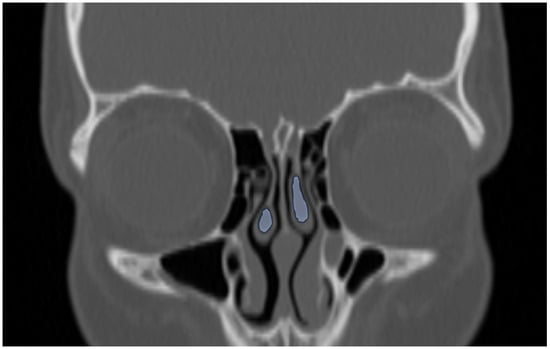

Figure 4.

Sagittal reformatted CT image of a 14-year-old girl showing Agger Nasi cell (orange area) in front of the frontal recess draining into the middle meatus (curved arrow) and concha bullosa (blue area).

Coronal reformatted CT image of a 12-year-old boy demonstrating bilateral concha bullosa in the middle turbinate (blue areas).

Additionally, the images were assessed for the presence of anatomic variants of the nasal cavity and PNS. Sinonasal variations were defined based on the European Position Paper on the Anatomical Terminology of the Internal Nose and Paranasal Sinuses [19]. According to this paper, the maxillary sinus is located between the orbital floor and alveolar process of the maxilla; the sphenoid sinus is the pneumatization of the sphenoid bone posterior to the rostrum; and the frontal sinus is defined as the pneumatization superior to a noticeable frontal beak [11,19]. The ANs are defined as the aeration of the protuberance on the lateral nasal wall, slightly anterior to the middle turbinate attachment (Figure 4). The Haller cell is an ethmoidal air cell, located below the orbital floor and lateral to a line parallel with the lamina papyracea (Figure 5). Onodi cell is the posteriorly located ethmoidal cell which develops just above and lateral to the sphenoid sinus (Figure 6). Concha bullosa is the pneumatization of the vertical segment of the middle turbinate (Figure 7) [19]. All anatomical variants were initially assessed by a single radiologist with four years of experience in maxillofacial CT imaging, who was blinded to patients’ demographic data, including age and sex. All assessments were done on a DICOM viewer (Medixant. RadiAnt DICOM Viewer [Software]. Version 2024.1. URL: https://www.radiantviewer.com (accessed on 1 November 2024)), after retrieval from the hospital PACS system to provide anonymized evaluation. The prevalence of each variant and the frequency of its bilaterality in each group were recorded. The evaluations were subsequently reviewed by a second radiologist with 11 years of experience. In cases of uncertainty regarding the presence of anatomical variations, a consensus decision was reached in consultation with a third radiologist with 13 years of experience.

Consistent with previous studies, the most frequent anatomic variant in our study group was ANs (58.8%), which are known to be present at birth and were observed with similar frequency across all age groups [7,8]. Although the reported prevalence of ANs in the literature varies widely, ranging from 3% to 100%, it is often listed among the three most common sinonasal variants [7,8,20,21]. Pneumatization of these cells has been hypothesized to narrow the frontal recess, potentially impairing the drainage of the frontal sinus and contributing to the development of frontal sinusitis. However, previous studies have found no significant difference in the prevalence of ANs between patients with and without clinically diagnosed frontal rhinosinusitis [7,22]. Similarly, in our study, no significant difference was observed in sinus volumes between individuals with and without ANs, suggesting that their presence does not exert a substantial impact on frontal sinus pneumatization. Nevertheless, in an adult volumetric study, AN volume was reported to show a negative correlation with increasing age, indicating that age-related change should be considered during sinus surgery planning [23].